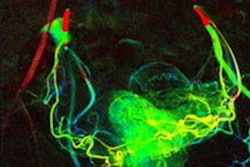

Pelvic (A), femoral and popliteal (B), and cruro-pedal (C) region. The summated digital variance angiography (DVA) image significantly enhances image quality compared to the digital subtraction angiography (DSA) series I–IV (depicting 4 out of 28 (A), 48 (B) and 28 (C) DSA images) of the low dose (LD) acquisitions. Enhancements of iodinated contrast medium (ICM) by DVA depict small vessel structures in detail while the conventional DSA offers a reduced contrast-to-noise ratio (CNR) using LD acquisitions for standalone diagnostic interpretations.Scientific Reports

According to the analysis, overall DAP was significantly reduced in the DVA group from 3238.6 cGy·cm² to 1230.4 cGy·cm² in pelvic regions, from 1190.9 cGy·cm² to 550.8 cGy·cm² in femoral and popliteal regions, and from 827.6 cGy·cm² to 336.0 cGy·cm² in cruropedal regions.

In addition, DVA images exhibited substantially enhanced ICM contrast and decreased background noise in all regions, the group reported. Specifically, median CNRs in ROIs in the DVA group increased significantly from 8.8 to 14.4 in pelvic regions, from 6.9 to 17.8 in femoral and popliteal regions, and from 7.8 to 17.3 in cruropedal regions.